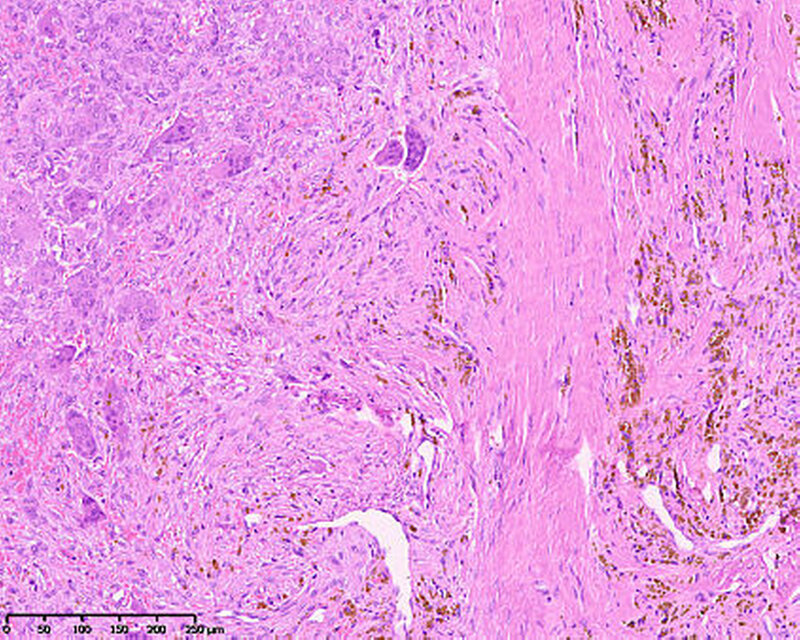

Die histopathologische Untersuchung ergab eine riesenzellbildende Läsion, so dass eine rein histopathologische Unterscheidung zwischen zentralem beziehungsweise peripherem Riesenzellgranulom und einem braunen Tumor nicht möglich war. Die weiterführende laborchemische Diagnostik ergab ein erhöhtes Parathormon im Serum 148,2 pg/ml (Norm: 15,0 bis 68,3 pg/ml) und ein normales Serumkalzium von 2,38 mmol/l (2,20 bis 2,55 mmol/l), so dass in Zusammenschau aller Befunde von einem braunen Tumor bei renal sekundärem Hyperparathyreoidismus auszugehen ist.

Histopathologisch zeigen braune Tumore einen ähnlichen Aufbau wie Riesenzellgranulome beziehungsweise die solide Variante der aneurysmatischen Knochenzyste. Alle zeichnen sich durch das Vorhandensein von gefäßreichem Granulationsgewebe aus, in das zahlreiche mehrkernige osteoklastäre Riesenzellen eingebettet sind [Neville, 2009]. Hämosiderinbeladene Makrophagen führen zur typischen rötlich-braunen Farbe, die dem Tumor den Namen gegeben hat. Differenzialdiagnostisch bedarf es dann der laborchemischen Abklärung, um die Dia-gnose eines braunen Tumors stellen zu können. In der Regel werden Parathormon, Kalzium und Phosphat bestimmt.